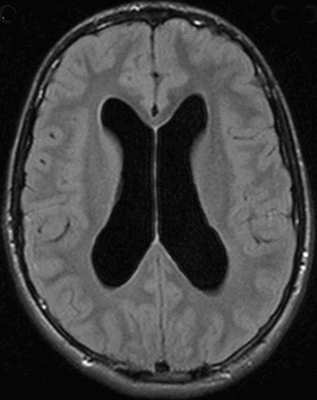

Гидроцефалия головного мозга на МРТ

Гидроцефалия на МРТ

Магнитно-резонансную томографию активно используют в неврологии и нейрохирургии. С помощью метода визуализируют головной мозг. Послойные снимки полноценно отражают церебральные структуры, позволяют выявить патологические изменения на любом участке и собрать детальные сведения об отклонениях.

МРТ имеет огромное значение для ранней диагностики заболеваний головного мозга. На снимках врач-рентгенолог видит признаки опасных для жизни состояний, например, водянки. Гидроцефалия головного мозга на МРТ проявляется характерными симптомами, даже на начальных этапах развития. Опытный диагност быстро определит патологию, установит форму, клиницист подберет правильную тактику лечения.

Внутренняя тривентрикулярная окклюзионная гидроцефалия на МРТ во фронтальной и сагиттальной плоскостях: на левом снимке видно гигантское кистозно-солидное образование, явившееся причиной обструкции ликворопроводящих путей на уровне Сильвиева водопровода

МРТ покажет гидроцефалию?

При магнитно-резонансной томографии получают послойные снимки исследуемой анатомической области. При изучении сканов врач видит мозговое вещество и выявляет отклонения от нормы. МРТ отчетливо показывает гидроцефалию. Метод информативен на ранних этапах развития заболевания, даже при отсутствии у пациента характерных симптомов. Детализация снимков позволяет врачам выявить водянку головного мозга, определить тип, диагностировать сопутствующие заболевания.

Водянка головного мозга при МР-сканировании в коронарной проекции

Признаки гидроцефалии у взрослых по МРТ

Проявления патологии на снимках бывают прямыми и косвенными. Первые связаны с расширением желудочков мозга (III, IV и боковых (в начальном периоде — в области передних рогов и тела)), водопровода и/или субарахноидального пространства (конвекситально, в области базальных цистерн, Сильвиевых борозд и пр.). Косвенные признаки на МР-сканах:

- межжелудочковый индекс свыше 0,5;

- перивентрикулярный отек при напряженной водянке;

- смещение гипоталамуса вниз;

- локальное выпячивание крыши боковых желудочков и др.

Дополнительно на томограммах определяют причину водянки головного мозга — основное заболевание.